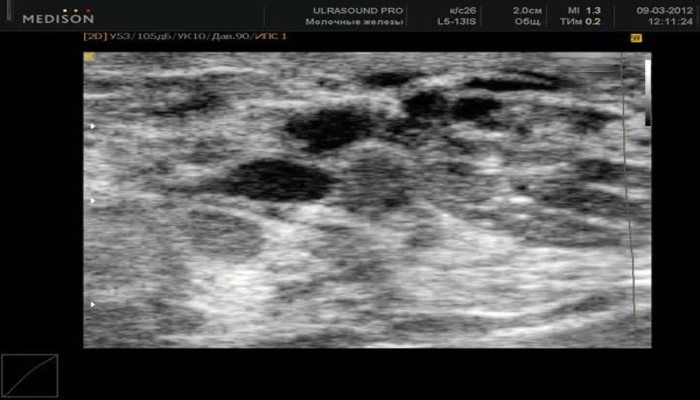

Диагностика включает в себя клинический осмотр врачом, ультразвуковое исследование молочных желез и, при необходимости, маммографию. В некоторых случаях может потребоваться биопсия для исключения злокачественных процессов.